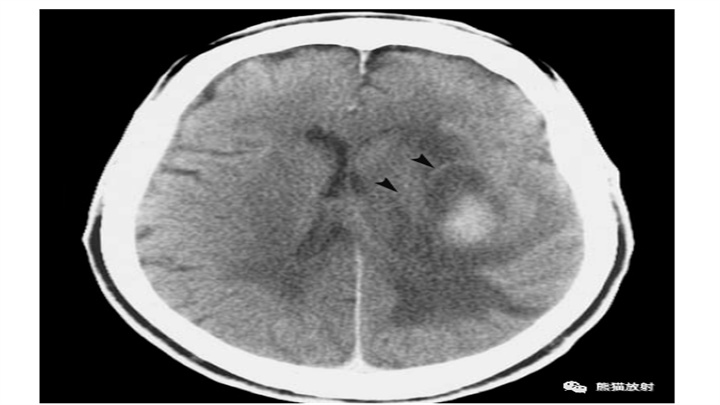

亚急性期血肿。大约两周以来,患者颅内高压症状持续恶化,左侧逐渐偏瘫。临床怀疑肿瘤。CT显示脑内血肿,不典型的部位(症状不典型);周围脑白质大量水肿,并具有明显占位效应。增强扫描表现强烈提示出血(经后续检查证实)。周围可见强化的不规则环,细且规则。该患者尚未接受类固醇的治疗。